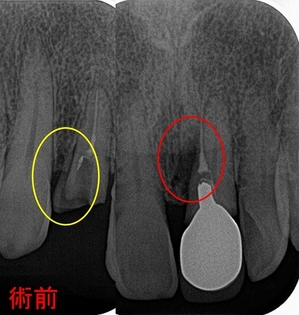

術前

右上2:メタルコアによる歯根破折

左上1:神経管と異なる所を削ったことによるパフォレーション(フィステルあり)